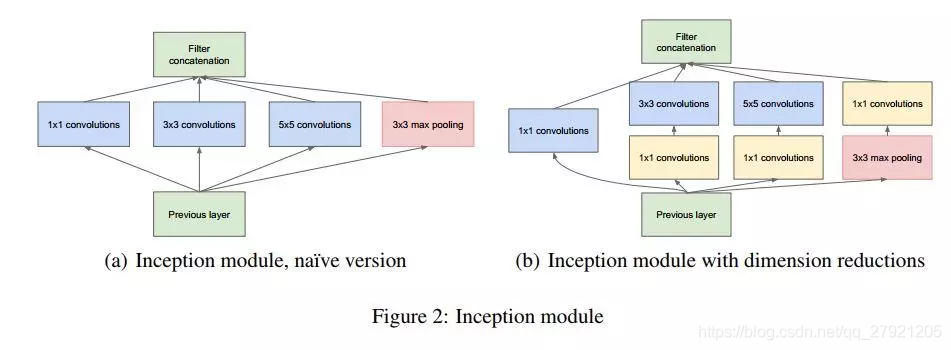

inception介绍

[v1] Going Deeper with Convolutions, 6.67% test error, http://arxiv.org/abs/1409.4842

[v2] Batch Normalization: Accelerating Deep Network Training by Reducing Internal Covariate Shift, 4.8% test error, http://arxiv.org/abs/1502.03167

[v3] Rethinking the Inception Architecture for Computer Vision, 3.5% test error, http://arxiv.org/abs/1512.00567

[v4] Inception-v4, Inception-ResNet and the Impact of Residual Connections on Learning, 3.08% test error, http://arxiv.org/abs/1602.07261

v1:使用多种尺度的卷积核,使用1*1卷积用于降维。可以解决对象在图片中的位置核尺寸差异问题。

v2:使用BN,使用33卷积代替55卷积。可实现收敛更快,参数更少。

v3:使用对称卷积。不过在中度大小的feature map上使用效果才会更好,对于mxm大小的feature map,建议m在12到20之间。